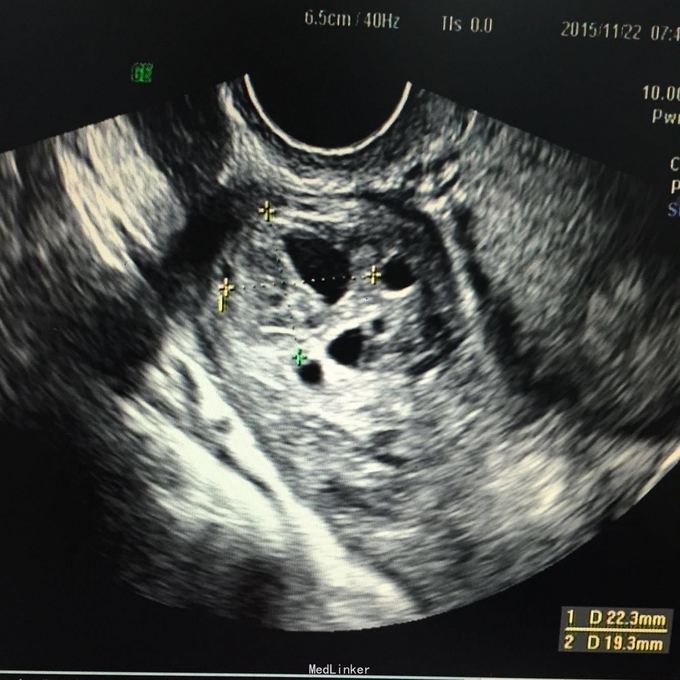

查体:生命体征平稳,腹肌紧张,右侧附件区轻压痛,无反跳痛。入院后完善彩超:右侧卵巢小囊,22*19mm,考虑黄体可能性大。盆腔混合回声团,考虑凝血块,范围约89*45mm,腹腔积液,最大深度:侧腹部37mm。